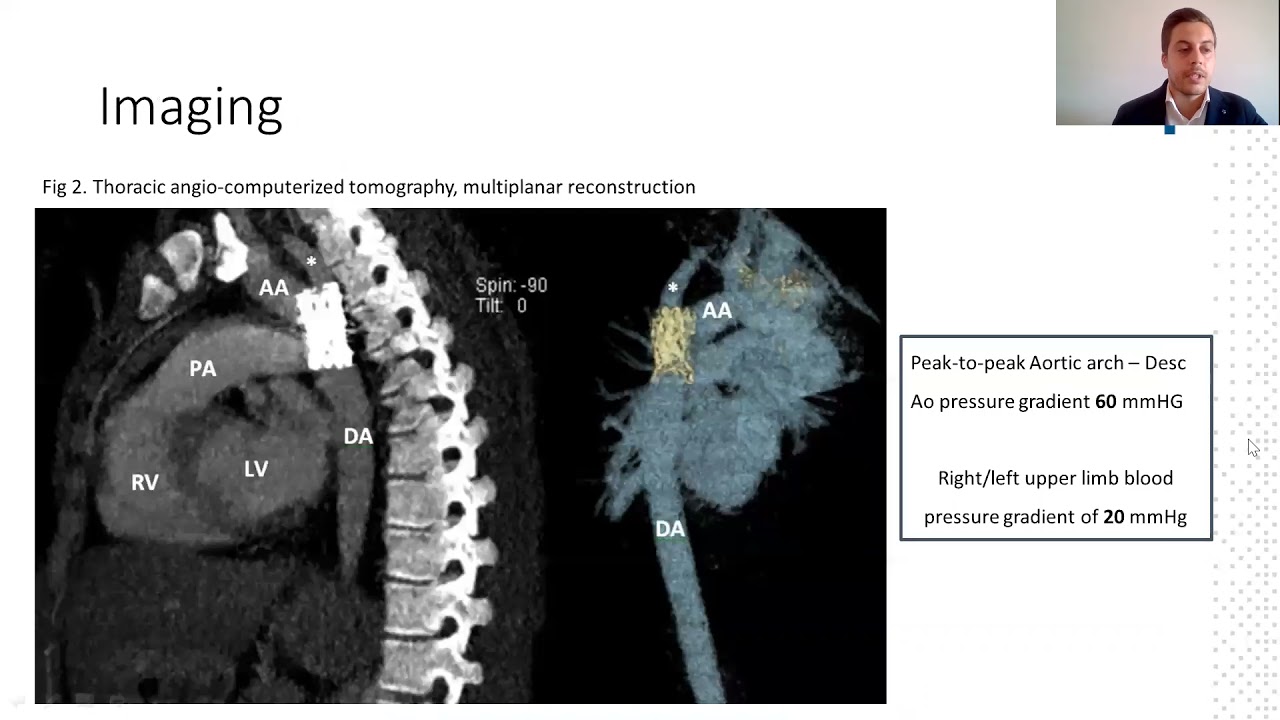

How should you treat coarctation and aortic stenosis in an adult with very high surgical risk?

By: Luis Fernandez Gonzalez, Hospital Universitario de Cruces, Baracaldo, Spain